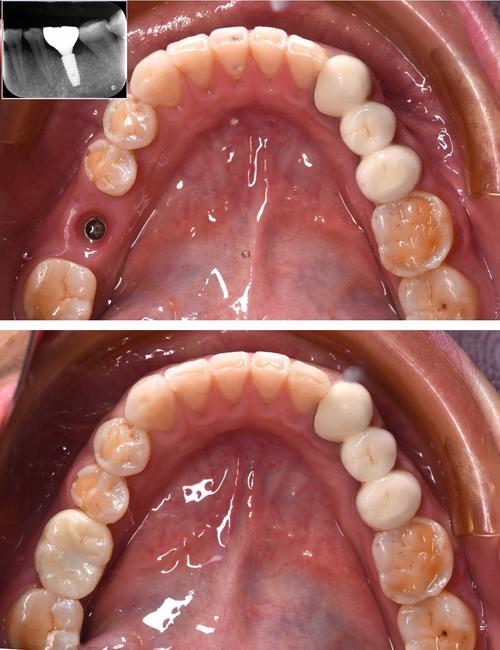

- 植入种植体: 将两颗纯钛(或钛合金)的种植体(人工牙根)旋入或压入制备好的窝洞中,医生会确保植入位置、角度、深度精确无误。

- 愈合期: 手术后需要等待3-6个月(具体时间因人而异,取决于骨密度、是否植骨等),让种植体与牙槽骨发生牢固的骨结合(Osseointegration),期间医生会安排复查。

- 取模与制作牙冠: 当种植体稳定、牙龈形态良好后,医生会取模,由牙科技工室制作最终的牙冠(可以是烤瓷冠、全瓷冠或金属烤瓷冠),对于两颗相邻的种植体,牙冠通常是连接在一起的(称为“桥”或“联冠”)。

- 戴牙: 将制作好的牙冠/桥通过基台或直接连接在种植体上,完成修复。